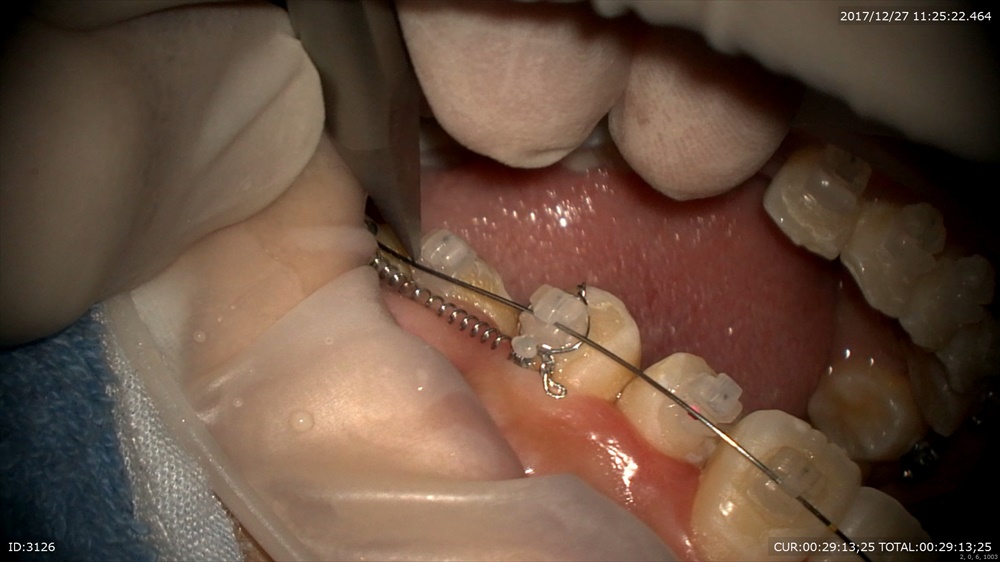

次は矯正治療

犬歯の移動が進み側切歯の移動です。痛みが少ないデーモン!

よっと。かかった!

ガタガタとはおさらばですね。